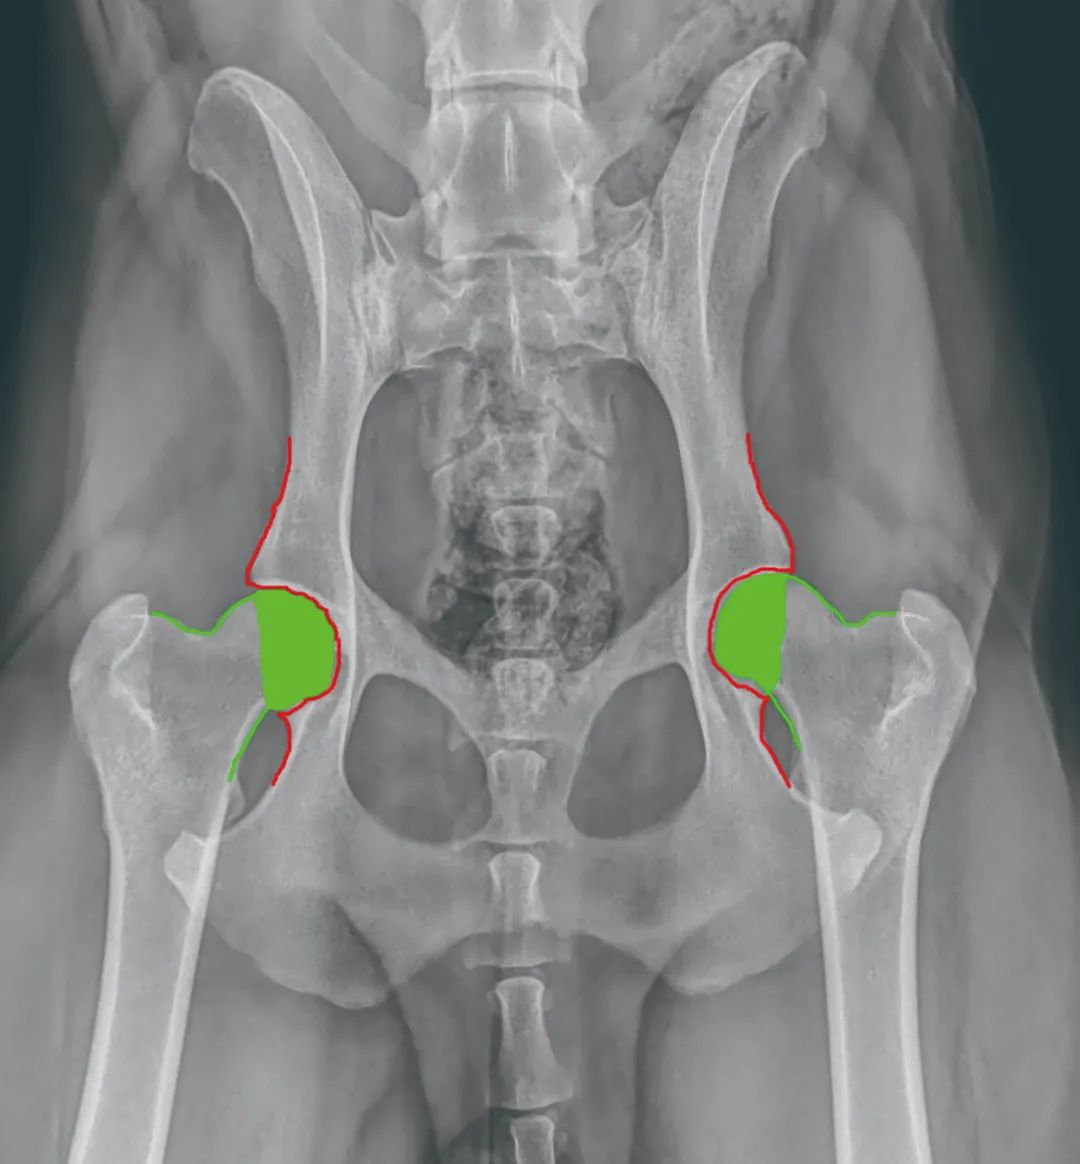

犬髋关节发育不良,简称CHD,是一种有基因参与的关节疾病。病灶在狗的髋关节,髋关节是狗狗后腿和盆骨的连接处。

狗的髋关节由两个部分组成,髋臼(acetabulum)和股骨头(femoralhead)。大腿骨顶部的股骨头嵌入髋臼,两个部位之间存在结实的韧带和软骨层保证紧密结合,让关节承受很大重量的同时又能灵活运动。如果这些结构出问题,股骨头和髋臼无法正常互动,CHD就此出现。

当髋臼和股骨头之间的韧带、软骨组织这二者出现问题,髋关节的紧密嵌合不复存在,犬只在行动时会产生磨损。时间越久,髋关节会出现结构上的改变,这时候CHD造就的骨关节炎可能出现,炎症与疼痛开始困扰狗狗,使得狗狗在很多行动上出现不正常的举止。

韧带组织:在股骨头正中、周边,都存在有强壮的韧带组织,将股骨头牢牢牵在髋臼里。患有CHD的狗,这部分韧带出现松弛,使得股骨头和髋臼之间出现松动与滑脱。

软骨组织:在关节之间又有一层厚厚的软骨。也叫关节软骨,正是这种滑滑的结构,保证着关节之间能平顺活动。在患有CHD的狗狗身上,这层软骨出现了破损、侵蚀,关节运作不再是软骨对软骨,而是骨头蹭骨头硬碰硬。久而久之髋关节会变形、扭曲。

3、医生常规的诊断是通过X光进行确诊,但有时在早期时通过X光检查,不会出现严重的关节磨损现象。这时可以根据医生的建议 进行一些骨关节保健品的补充使用 ,建议一定在医生的建议下用药、用保健品。